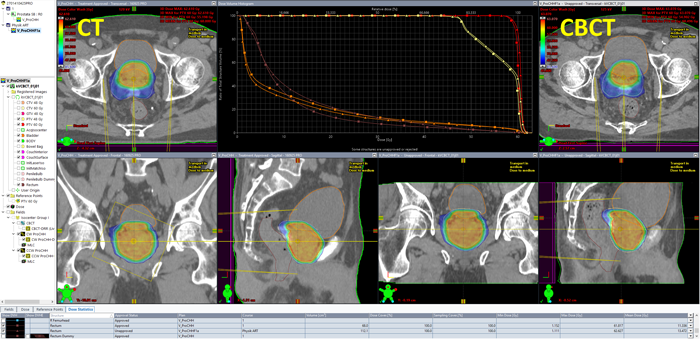

The patient anatomy shown in the first image belongs to a prostate plan with the CHHiP prescription 20 x 3 Gy = 60 Gy to the (central) high dose region, 48 Gy to the periphery. The hydrogel which was used to push the rectum away from the high dose region is also visible.

During the first session, we asked the therapists to aquire a Pelvis scan instead of the Spotlight they would normally choose. During CBCT aquisition, the PerfectPitch couch is always levelled (Pitch = Roll = 0.0°). Then an online match against the planning CT is performed, followed by a 6 DoF couch shift, followed by the treatment.

The elegance of the integrated Varian system is that as soon as the treatment session on the TrueBeam is closed, the CBCT image can be opened on any Eclipse workstation on the network (no export). Immediately after the treatment, we performed the following steps in order to get dose calculated on today's CBCT:

Dose on the CBCT is calculated with the same parameters as in the treatment approved plan (AXB, 2mm grid). Since the patient had no metal implants, we skipped the "Segment High Density Artifacts" step in Contouring. Consequently, no material assignment was necessary.

It is good to see that target doses (DVH curves in red and yellow) are very close: in today's session (triangles) the mean PTV60 dose was 60.496 Gy (+0.8%), whereas the original plan (squares) had been normalized to target mean (60.000 Gy).

During contouring of the CBCT, we had already seen that the rectum - in spite of the SpaceOAR hydrogel - was a little closer to the high dose region than in the planning CT. This is confirmed by its mean dose, which is a little higher:

All dose values are for 20 sessions. A mean dose of 13.472 Gy instead of the 11.336 Gy in the original plan means that if the anatomic situation in all 20 sessions would be as it was today, rectum mean dose would be 2.1 Gy higher than planned. We all know that this is unlikely. This is exactly what a good ART management system should provide: keeping track of all the doses for (example) 20 individual plans with 20 individual sets of DVHs.